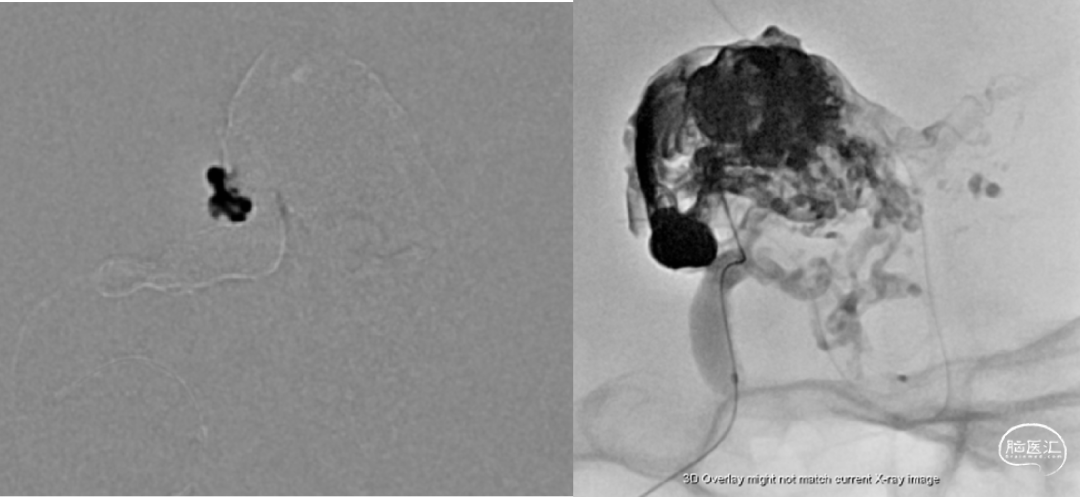

术前检查

🔹治疗方案:全麻下经静脉入路脑动静脉畸形栓塞术

经静脉入路超选到位

经Echlon10微导管填入弹簧圈做塞子

经Apllo微导管注入Onyx胶